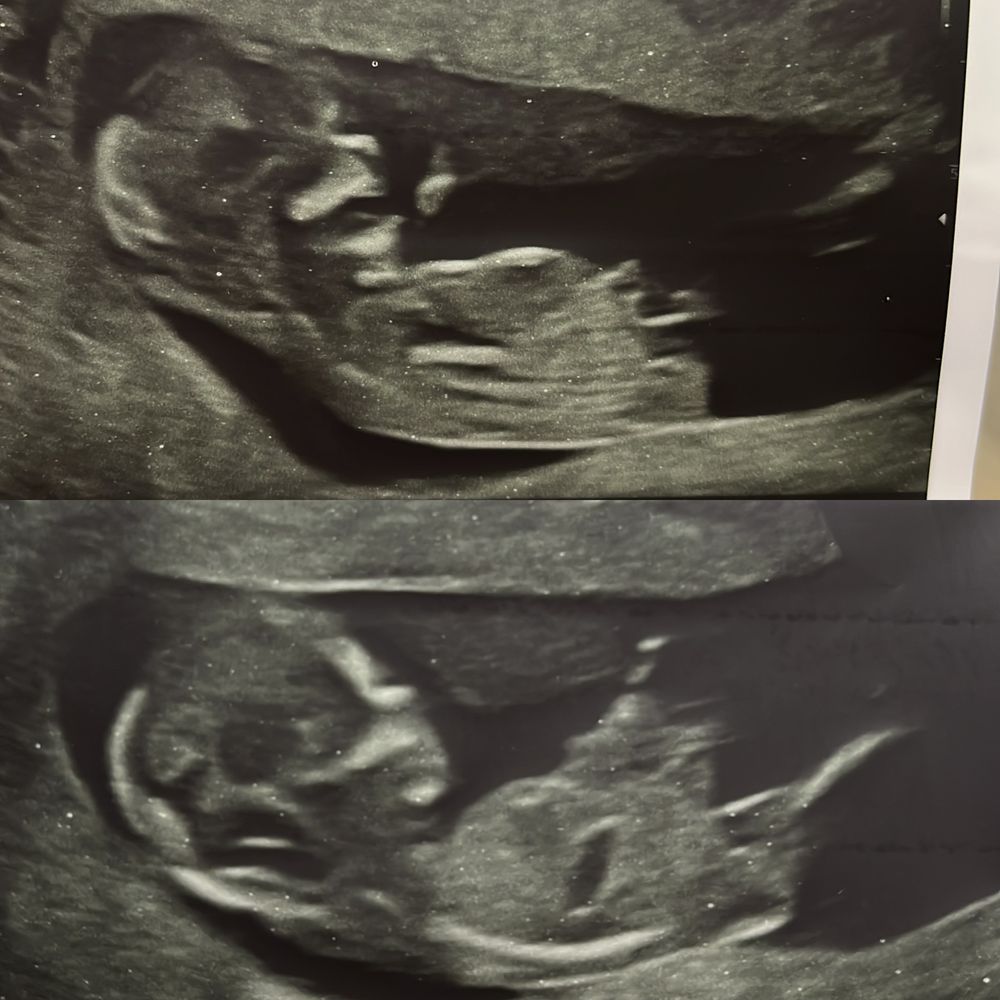

с дочкой было все четко , вот:

Но на экране было четче ,печать более смазанная

А у меня вроде бы и четко, но ни бугорка, ничего не видно😁